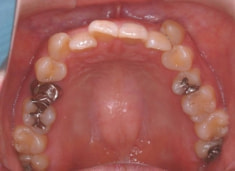

治療後(2年5ヶ月後)

治療開始から約1年2ヶ月後